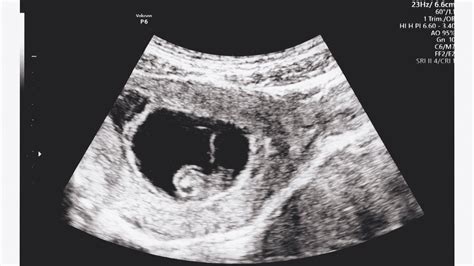

Általában a beültetés után 10-12 nappal otthoni terhességi teszt segítségével kimutatható, hogy sikeres volt-e a kezelés. Ugyanakkor a legbiztosabban vérvétellel igazolható a terhességi hormon jelenléte, majd egy-két héttel később ultrahanggal mutatható ki a klinikai terhesség.